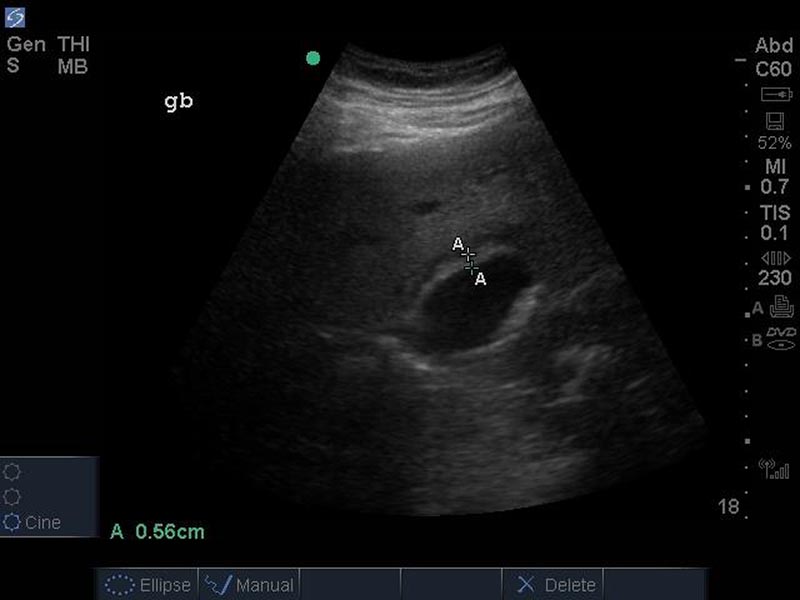

40 y/o female with history of hyperlipidemia, obesity, and GERD presenting with upper abdominal pain. The goals of this case are to evaluate initial evaluation of young female with upper abdominal pain and review ultrasound findings of acute.